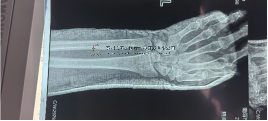

本病例由中國中醫(yī)科學(xué)院望京醫(yī)院骨創(chuàng)傷一科提供

【基本資料】患者,男,64歲

術(shù)前X片